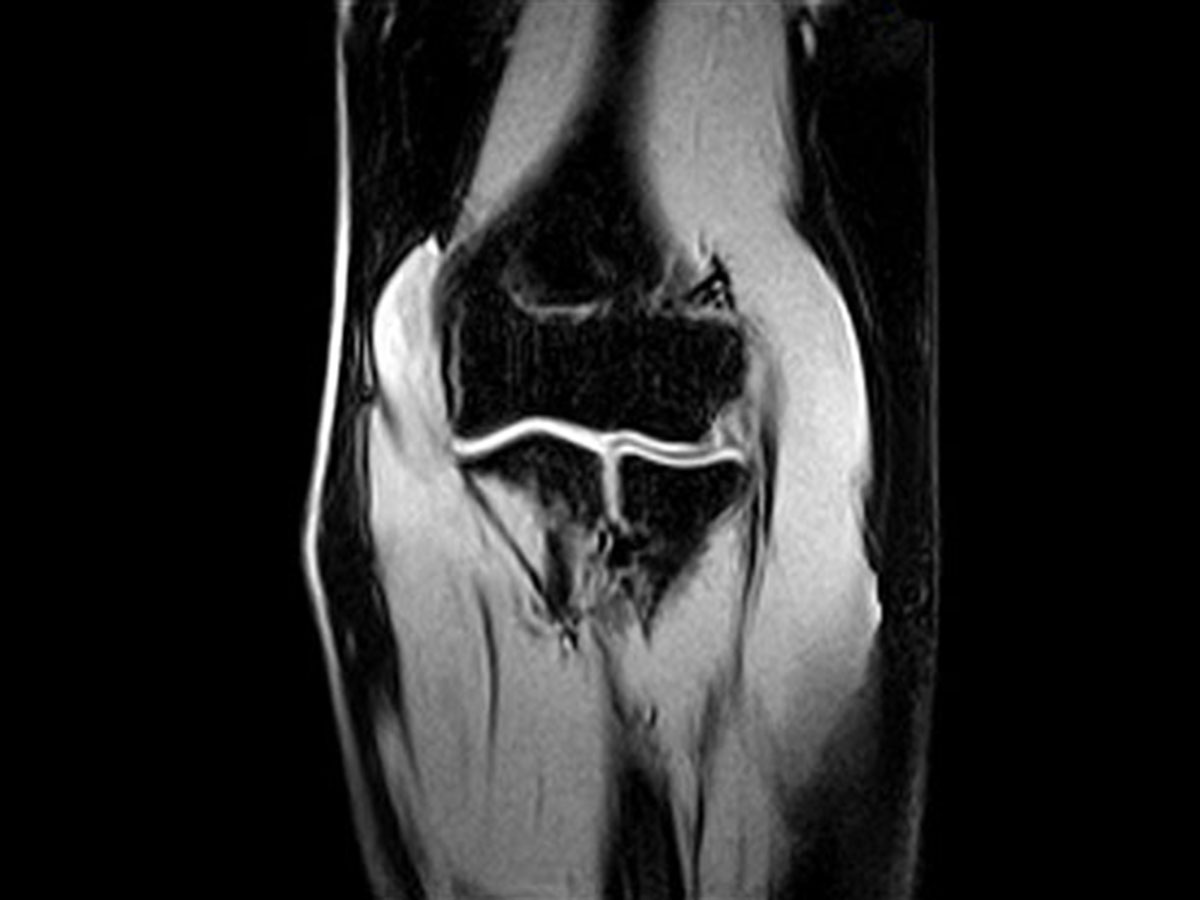

■ O-scan hviezda medzi MRI končatín, počíta s potrebou vyššej priepustnosti v rádiológii a ortopedickej praxi. Môže ľahko pracovať po boku celotelových skenerov na rádiologických pracoviskách a tak ušetriť čas pre veľké klinické prípady, čím umožní zlepšenie workflow a zabezpečenie optimálnej starostlivosti o pacienta.

■ Vysokokvalitné spoločné MRI vyšetrenia za oveľa konkurencieschopnejšie ceny než u štandardných celotelových MRI systémov

■ Vďaka inovatívnej a špeciálnej technológii je Esaote lídrom v oblasti vyhradenej muskuloskeletálnej MRI s viac ako 2000 systémami inštalovanými po celom svete. Neustále sa rozrastajúca rodina inovatívnych špecializovaných MRI systémov sa môže pochváliť spoločnými rysmi, ako je jednoduché použitie, otvorený ergonomický dizajn, ktorý zaručuje optimálny komfort pre pacienta a efektívnosť nákladov.